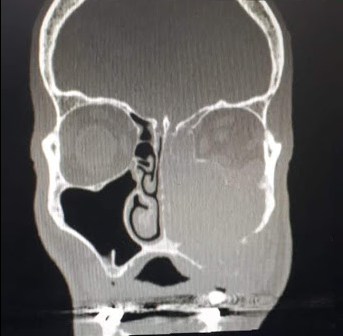

ESTUDIOS PARACLÍNICOS: Se solicita TOMOGRAFÍA DE ÓRBITA y de SENOS PARANASALES.